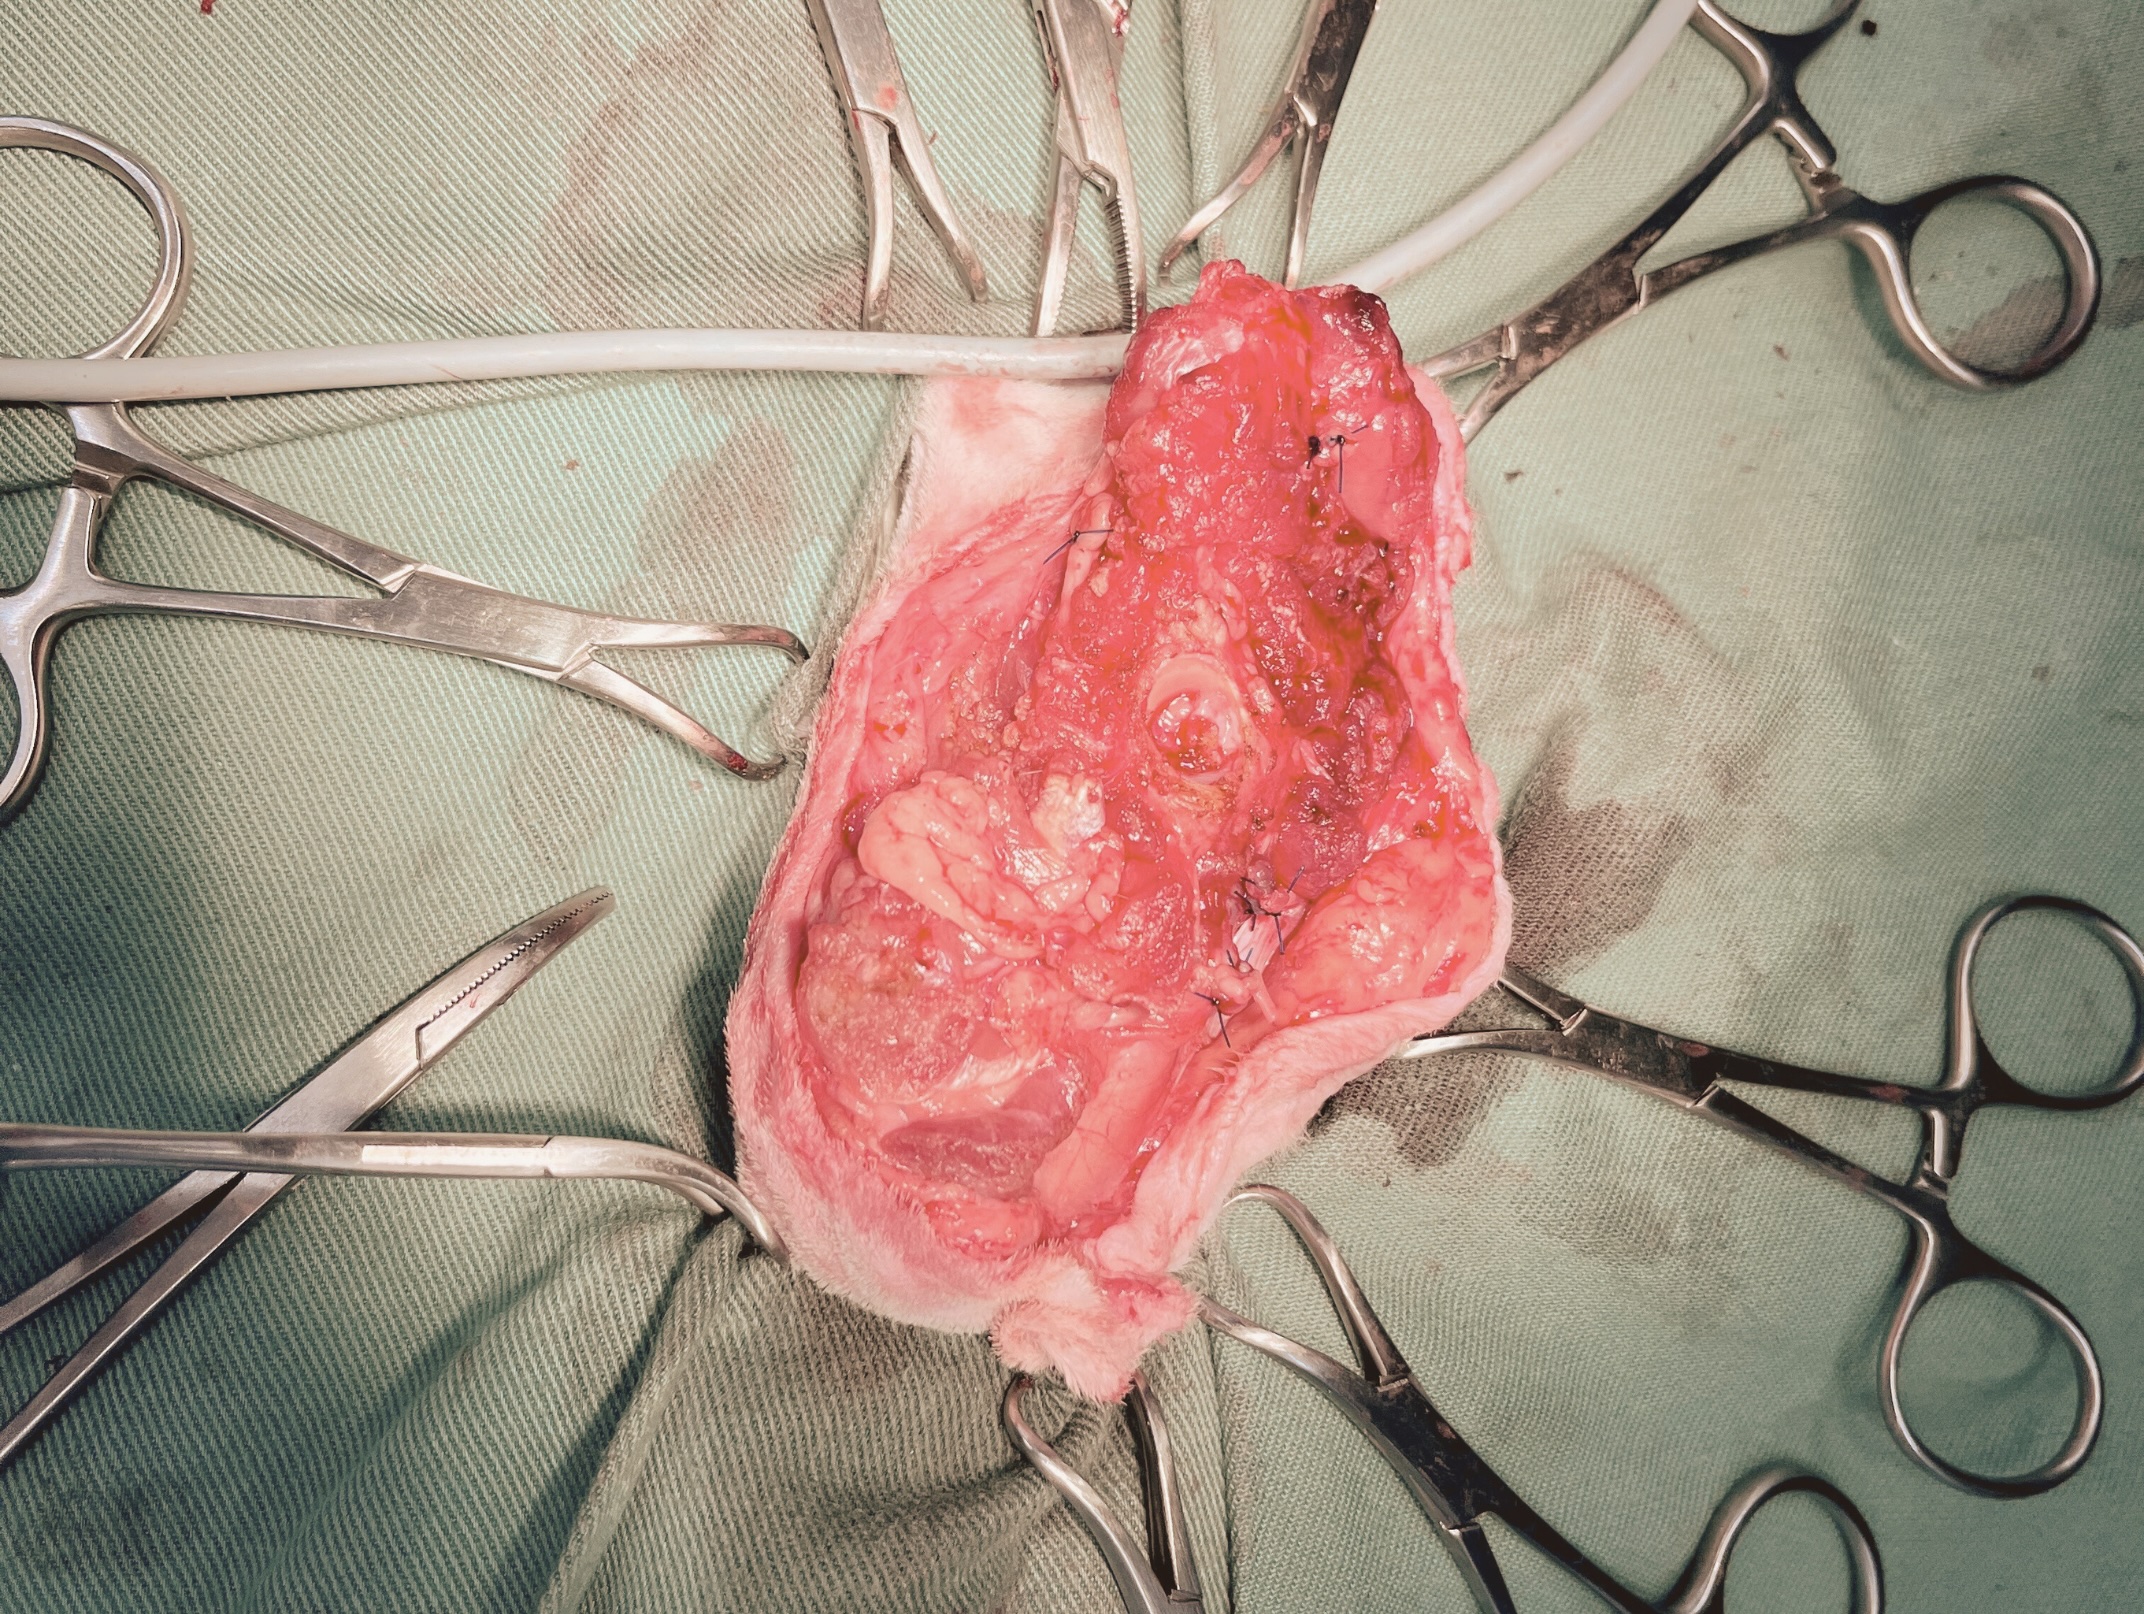

飼い主様とご相談のうえ、痛みの除去と生活の質の改善、さらに完治を目指す治療として、股関節レベルでの断脚手術を行う方針としました。

こちらが手術前と手術中の写真です。

手術は無事に終了し、術後の経過も良好でした。

こちらが術後の患者の様子と、断脚を行った脚の写真です。

大きな合併症もなく、術後まもなく歩行も可能となり、日常生活に支障なく過ごすことができました。